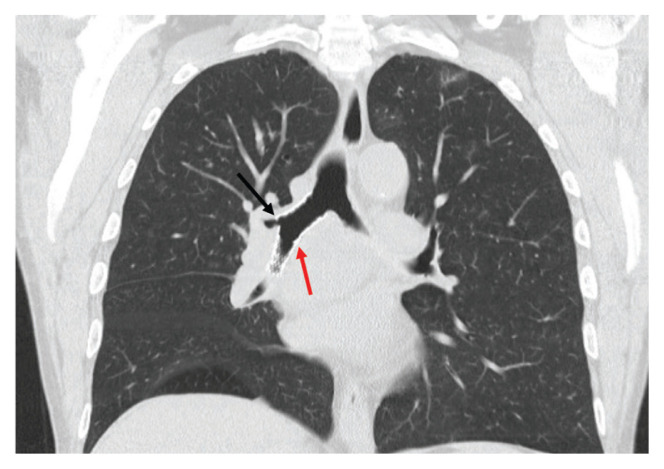

A 65-year-old veteran with a history of smoking presented to a US Department of Veterans Affairs Medical Center (VAMC) in 2011, with hemoptysis of 2-week duration. Computed tomography (CT) of the chest revealed a 5.3 × 4.2 × 6.5 cm right mediastinal mass and a 3.0 × 2.8 × 3 cm right hilar mass. Flexible bronchoscopy revealed > 80% occlusion of the RMS and BI due to a medially located mass sparing the RUL orifice, which was patent (Figure 1). Airways distal to the BI were free of disease. Endobronchial biopsies revealed poorly differentiated non-small cell carcinoma of the lung. The patient was referred to the interventional pulmonary service for further airway management.

FIGURE 1. Tumor Mass on Coronal Section of Chest Computed Tomography.

Arrow indicated tumor mass, which is medially located and obstructs the right mainstem and bronchus intermedius but spares the right upper lobe bronchus.